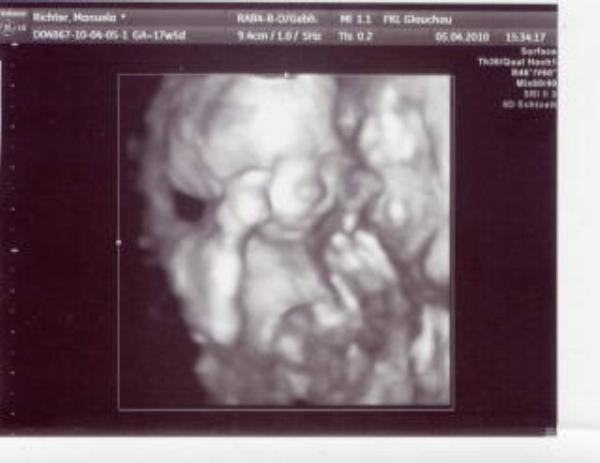

Hallo Mädels, mein Ostern war alles andere als langweilig. Erst durfte ich ins Kh am Freitag mit meiner Maus angehende Angina und Kehlkopfentzündung. Naja gut haben was bekomm nach std warten und bis jetzt gehts ihr ganz gut. Nun sprang mir am Sonntag mein kleiner Mann auf den Bauch auwa Bin dann ins KH haben TG gemacht, Herztöne waren leider nicht durchgehend zu hören. Aber keine Wehen, dann US soweit alles ok, dann meinte die Ärztin sollte Montag wieder komm weil sich der Mutterkuchen ablösen kann. na toll dachte ich muss man echt haben. Und Outings gabs nicht aber liegt nicht mehr quer sondern SL. Naja war heute wieder gleich US 20 min Baby TV, das war schön, war zum glück alles ok und vom Outing her vermutung auf Junge (schaute sogar obs die Nabelschnur ist - wars aber nicht), dann drehte sich mein Zwerg und da war die Nudel wieder weg. Da macht sie noch 4D und nein immer Arme und Beine davor. Toll, aber sie bleibt bei Vermutung Junge. Morgen darf ich nochmal zur Kontrolle zum FA und mal schauen was er dann zum outing sagt. Mein Mäusel hält mich ganz schön hin.... also Tee trinken und warten wie immer. Mausi ist ca 21cm gross. Im Anschluss ein Bildchen noch. Lg Manu hoffe euer Ostern war nicht so aufregend!!!

Bild zu Muss jetz auch mal mein Senf zu mein Ostern beitragen - Forum für September - Mamis